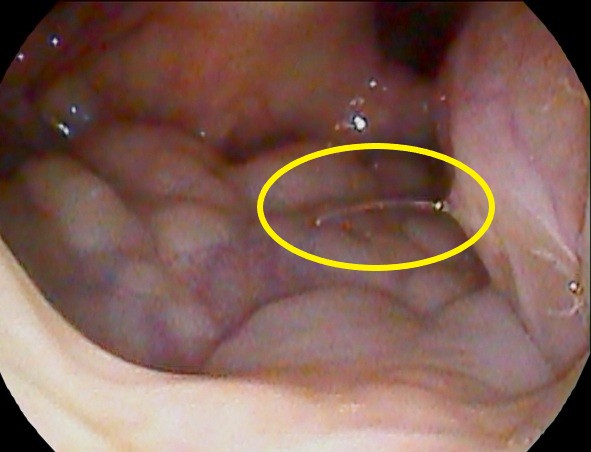

この位置です↓

この黄色の丸印です。

鉗子付きファイバーで摘出しました。